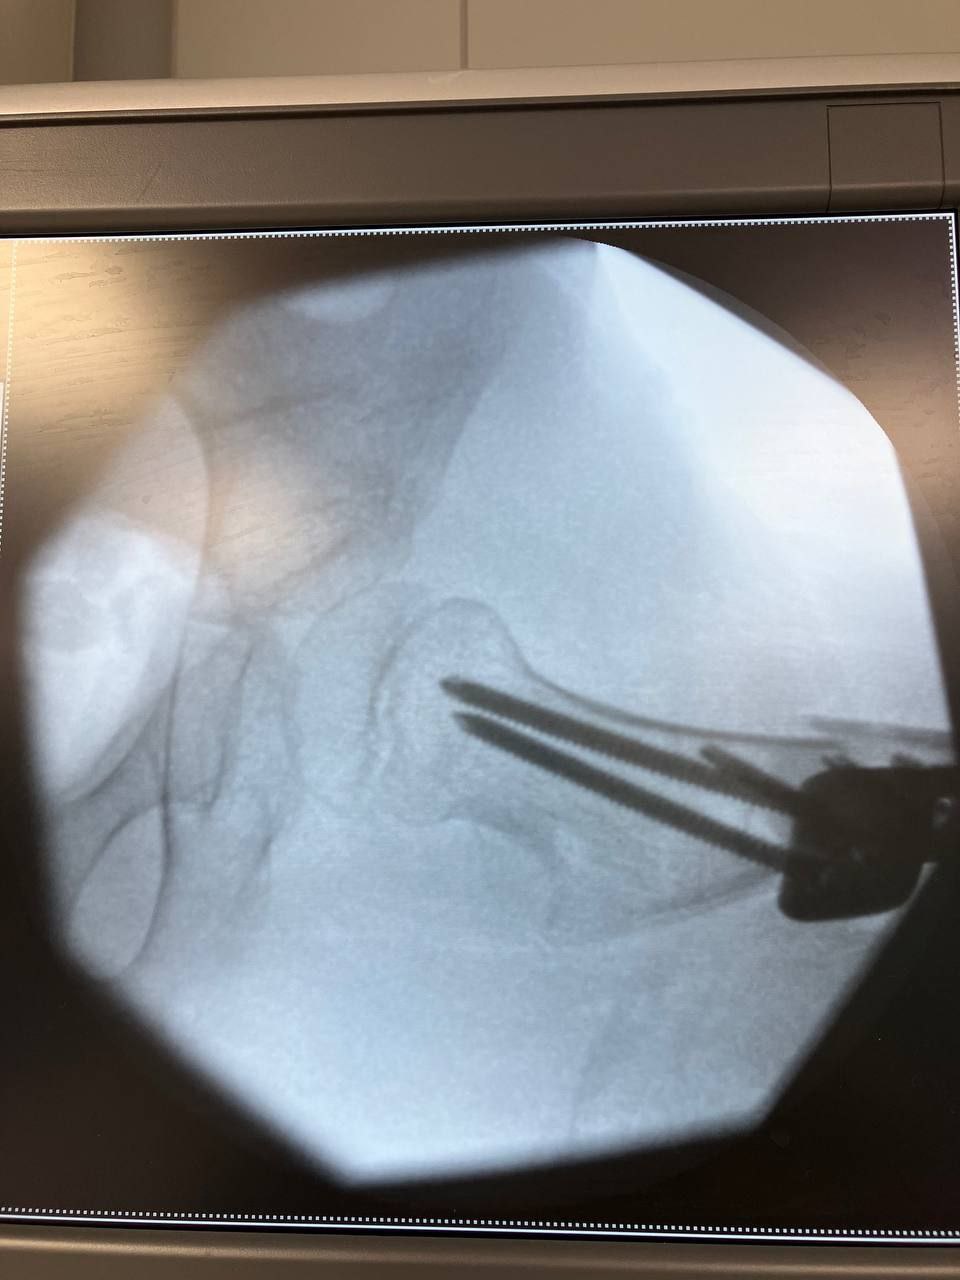

Через прогресуючі вивихи кульшових суглобів йому була життєво необхідна термінова ортопедична операція.

БФ "Бонум Україна" оплатив хірургічне втручання та необхідні імпланти, а лікарі провели коригувальну остеотомію стегнової кістки з фіксацією пластиною та остеотомію таза за Дега.